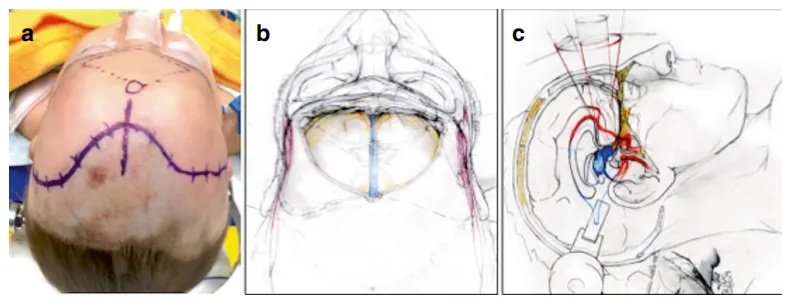

菲恩被安置于专用手术台(图c),INC巴教授经额底正中入路,在术中MRI(iMRI)辅助下行肿瘤切除术。

这一台手术巴教授采用的是额底正中开颅-纵裂入路(Frontobasal Midline Craniotomy and Interhemispheric Approach)。

【图示:中线入路时,患者取仰卧位,于发际后方作弧形皮肤切口(图a)。开颅呈对称三角形,骨窗下缘紧邻眶顶(图b)。经额叶纵裂可直达视交叉-下丘脑区及完整显露Willis环(图c)。】

该入路可提供下丘脑区域全景视野,既能垂直、对称地深入第三脑室,又可直达脚间池及鞍区。虽与眶颧入路同样费时费力,但美容效果同样满意。